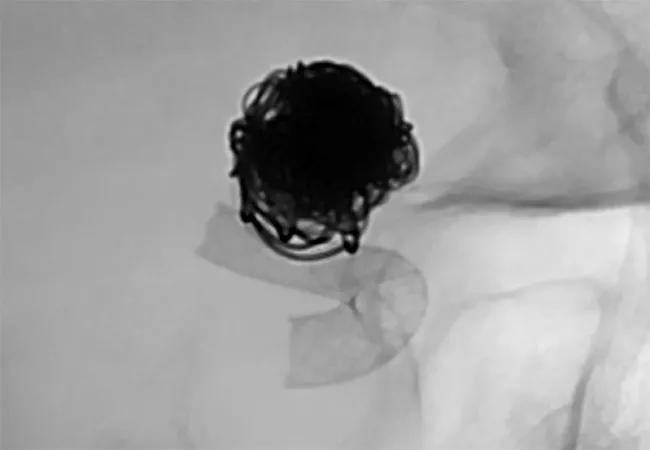

First we performed a cerebral angiogram with conventional endovascular coiling, passing a catheter through her groin into the artery containing the aneurysm and then releasing platinum coils to induce clotting. This was standard therapy before the advent of flow diverters, but coiling tends not to work well in larger aneurysms. In this patient’s case, however, that approach gave us an opportunity to stabilize the aneurysm for the short term.

She stayed in the neurological intensive care unit for two weeks, during which time she required a ventricular shunt to drain fluid from her brain. Following placement of the shunt, we were able to start her on aspirin and clopidogrel to prevent clots from forming within the flow diverter device. Once her medications were on board, we performed a second angiogram using the Surpass Streamline™ Flow Diverter (Stryker) to restrict blood from entering the aneurysmal sac, thereby promoting clotting within the aneurysm. The procedure took approximately 30 minutes.